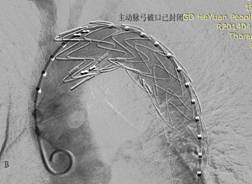

图1 患者男,46岁,胸痛5小时急诊入院,诊断为主动脉夹层(Standford B型),入院1周后行主动脉夹层腔内修复术,术后1周临床治愈出院。A为治疗前造影,B为覆膜支架修复破裂口后。